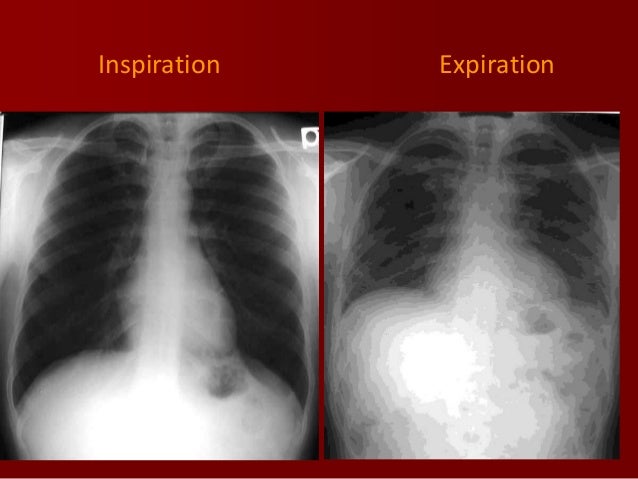

BASICS OF CHEST X RAY PART3 INSPIRATION VS EXPIRATION QUALITY OF X RAY

This may result from a poor inspiratory effort or any other condition that prevents full inspiration This patient s chest x ray is normal in full inspiration In relative expiration the cardiac Results The breathing with mainly inspiration group BMIG showed significant differences in chest size during inspiration CSI chest expansion values CEVs forced vital capacity